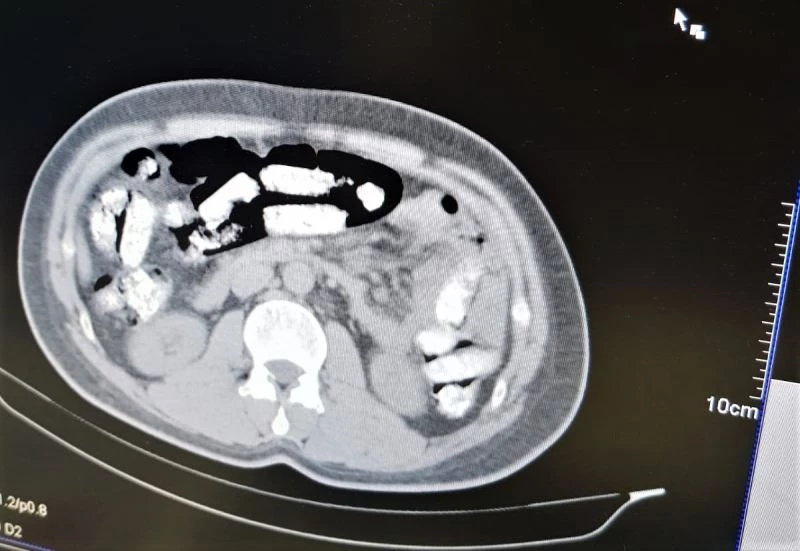

Erzincan’da narkotik polislerinin yaptığı yol uygulaması sırasında durdurulan otobüste, uyuşturucuyu midesine gizleyen İran uyruklu 1 kişi tutuklandı. Tutuklanan zanlının bedeninden 1 kilo 198 gram Afyon Sakızı ele geçirildi.

Erzincan İl Emniyet Müdürlüğü Narkotik Suçlarla Mücadele Şube Müdürlüğü ekiplerince uyuşturucu madde kuryeliği yapan şahıslara yönelik İran otobüsleri üzerinde yapılan uygulamada; İran otobüsünde yolculuk yapan Abdulmennan S. isimli İran uyruklu kişinin yutma yöntemiyle uyuşturucu taşıdığı değerlendirilmesi üzerine, Erzincan Mengücek Gazi Eğitim ve Araştırma Hastanesinde zanlının bedeninden 106 fişek halinde toplamda 1 kilo 198 gram Afyon Sakızı ele geçirildi. Abdulmennan S. hakkında TCK 188 suçundan yapılan tahkikat sonrası sevk edildiği mahkemece tutuklanarak cezaevine teslim gönderildi.